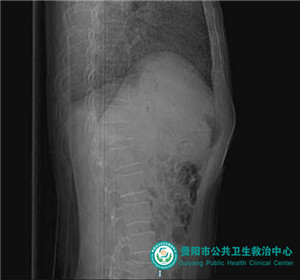

術(shù)后骨水泥充填椎體